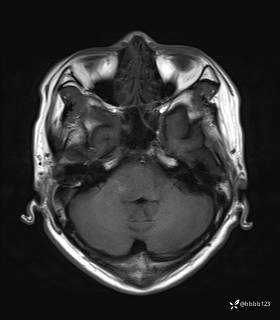

患者男,51岁。

简要病史:患者自述于1周前至某人民医院发现脑干肿瘤(具体不详),为求进一步诊断至我院就诊。

完善颅脑MRI平扫+增强,颅脑CT平扫:

T2: